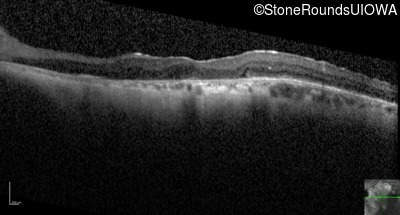

Optical Coherence Tomography - Right - 20/25 -2

Exemplar / OCT Stack